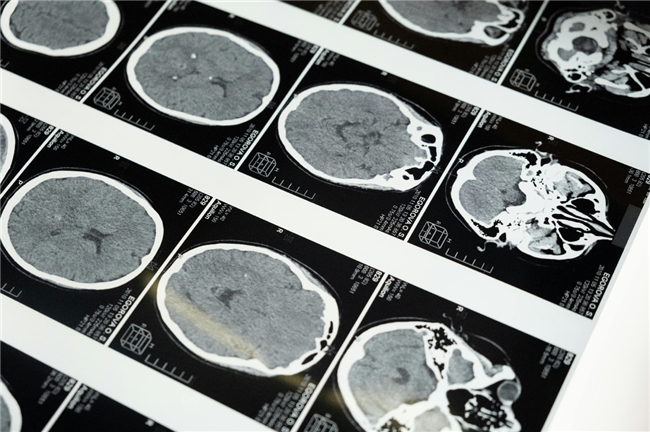

提到缺血性脑病,很多人会直接联想到“脑梗死”,但实际上,它是一个涵盖多种病理状态的“疾病家族”,核心特征均为“脑组织缺血缺氧”,但病情轻重、病程进展存在显著差异。从临床分类来看,缺血性脑病主要包括以下类型:一是短暂性脑缺血发作(TIA):俗称“小中风”,是脑血管的“临时堵塞”——堵塞物(如微小血栓)在数分钟至24小时内自行溶解,脑组织未出现不可逆损伤,患者可能出现短暂的肢体麻木、言语不清、视力模糊等症状,但多在24小时内完全恢复。二是缺血性脑梗死:也是最常见的类型,是脑血管“永久性堵塞”导致的脑组织坏死。当脑血管因动脉粥样硬化斑块破裂、血栓形成或外来栓塞(如心脏房颤形成的血栓脱落)发生堵塞,且堵塞物无法自行溶解时,对应的脑组织会因持续缺血缺氧逐渐坏死,形成“梗死灶”,患者会出现持续的神经功能障碍,如半身不遂、吞咽困难、认知障碍等,且损伤往往不可逆。三是脑分水岭梗死:发生在两条脑血管供血区域的“交界地带”,这类区域的脑组织供血本就相对薄弱,当全身血压降低(如休克、严重脱水)或脑血管狭窄加重时,容易先出现缺血缺氧。常见于老年人、合并低血压或严重血管狭窄的患者,症状多较轻,但复发风险较高。四是慢性缺血性脑病:由长期、慢性的脑供血不足导致,常见于高血压、糖尿病、脑小血管病患者。脑组织长期处于“低灌注”状态,会逐渐出现神经细胞缓慢坏死、脑白质疏松、脑萎缩等改变,患者早期可能仅表现为头晕、记忆力下降、乏力,后期可能进展为认知障碍、大小便失禁,严重影响生活质量。

无论哪种类型,缺血性脑病的本质都是“大脑能量供给与需求的失衡”——当脑血管无法满足脑组织的氧气和葡萄糖需求时,损伤便会启动。而了解这一损伤如何一步步发生,是科学干预的关键。针对缺血性脑病的发病机制,当前医学干预已形成“分阶段、多靶点”的全周期策略,涵盖急性期的“紧急抢救”、恢复期的“功能修复”和慢性期的“预防复发”,每个阶段的干预目标和手段各有侧重,但核心均围绕“改善供血、保护神经、减少损伤”展开。